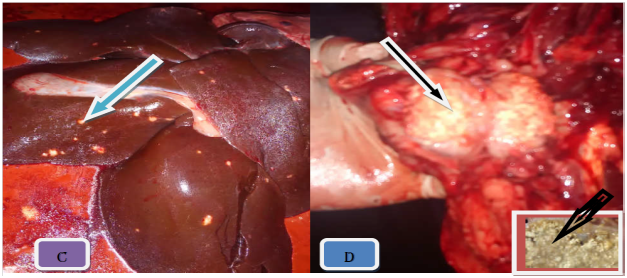

On the basis of gross pathology, in 556 slaughtered swine showed that 19.6% (109/556) were found to have tuberculous like lesions in parenchymatous organs of which 12% (69/556) were from lymph nodes, 5.7% (32/556) of the lungs, 1% (6/556) of the liver and 0.36% (2/556) of the spleen (Figure 2). The tuberculous like lesions found in lymph nodes, particularly those of mesenteric and retropharyngeal, were statistically significant (P < 0.05) than in lungs and associated lymph node. The majority of the lesions were considered to be of typical tuberculous lesions characterized by central round, oval, or irregular, often coalescing areas of caseous necrosis and calcification. The calcified lesions were exceedingly distributed in different lymph nodes and parts of the lungs (Figure 3).

Figure 3 Gross TB like lesion in different organs. Note: The typical caseuos calcified on left caudal lung (A), caseous exudates lesions in retropharyngeal lymph node (B), multifocal hepatic nodules (C), and typical caseous exudates in submandibular lymph node; after parafinized (black arrow) (D).